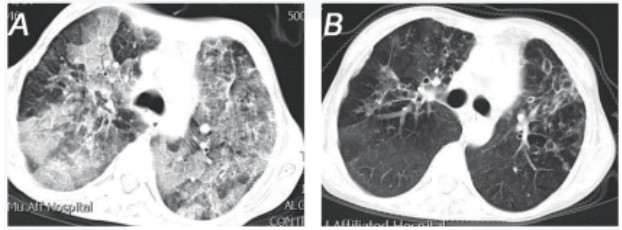

| A:患者入院肺部CT,提示双肺支气管扩张并感染,左肺部分不张;B:患者出院肺部CT,提示支气管扩张 图 1 患者肺部CT图像 |

患者女,31岁,因“咳嗽、咳痰伴腹胀3 d”于2019年2月4日转诊至遵义医科大学附属医院。入院前3 d,患者咳嗽、咳痰,发热39℃,伴腹胀、腹痛,就诊当地医院,考虑“肺部感染、脾大”,予抗感染治疗,无好转遂转院。患者既往史、个人史及流行病学史无特殊。查体:呼吸34次/min,体温39 ℃。双肺闻及湿性啰音,左腹部及脐周压痛,肋缘下10 cm触及脾脏,越过前正中线。胸部CT示支气管扩张并双肺感染,腹部CT示巨脾,体积1 755.064 mm3。白细胞(WBC)2.24×109/L,红细胞(RBC)2.71×1012/L,血小板(PLT)67×109/L,C反应蛋白(CRP)73.60 mg/L。入院诊断:(1)脓毒症、支气管扩张并感染;(2)三系(WBC、RBC、PLT)减少,原因:脾功能亢进;(3)巨脾。诊断依据:(1)患者临床表现及病史;(2)检查、检验结果;(3)sepsis 3.0,SOFA评分大于2分;(4)结核检测及胸部CT排除结核分枝杆菌感染,骨髓穿刺结果不支持血液及淋巴系统疾病,回顾患者既往病史及腹部CT图像排除肝硬化等疾病。多学科会诊:针对巨脾,考虑脓毒症所致充血性肿大,不考虑肝硬化及班替氏综合征,继续抗感染治疗, 菌培养+药敏结果提示哌拉西林舒巴坦钠、盐酸莫西沙星敏感的金黄色葡萄球菌,最终诊断:(1)脓毒症;(2)支气管扩张并感染;(3)巨脾;三系减少病因:脾功能亢进。再次根据药敏试验调整抗生素,患者体温恢复正常,脾脏体积出院时仅有641.545 mm3, 三系终于恢复正常范围,感染指标下降,好转出院。